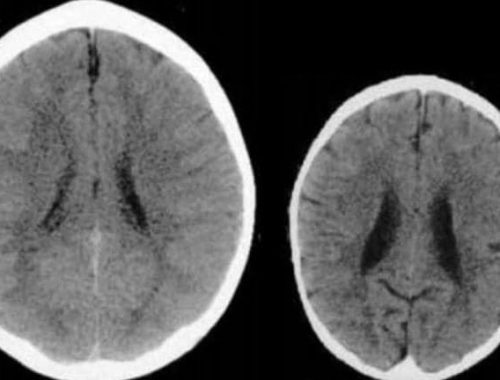

Egy brit kutatás olyan fiatal felnőtteket vizsgált, akik első éveiket romániai árvaházakban töltötték a kilencvenes évek elején. A tudósok tapasztalatai

Az érzelmi bántalmazás és elhanyagolás rendkívül súlyos hosszú távú következményekkel jár együtt: befolyásolja az agyműködést és a kognitív fejlődést, ráadásul